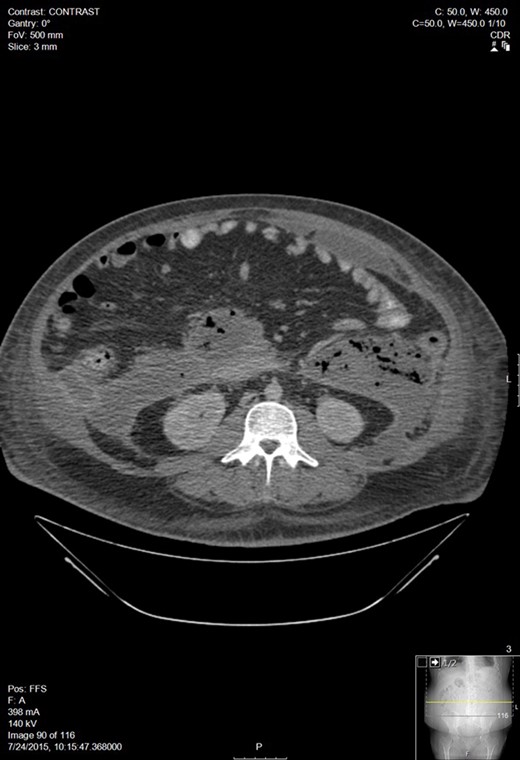

A week later, he presented to his PCP for follow up and was febrile with increasing abdominal pain. CT of the abdomen and pelvis showed an 11 × 15 cm2 pancreatic fluid collection. His hemoglobin was 6.9 and he was transfused 3 units of PRBC. After transfer to our facility, a repeat CT showed a small pericardial and left pleural effusions, large volume ascites, a pancreatic fluid collection within the lesser sac between the anterior pancreas and posterior gastric body measuring 14 × 16.1 × 16.2 cm3, and blood in both paracolic gutters and pararenal spaces (Fig. 2). He was referred to Interventional Radiology for drain placement. After drainage, he clinically improved and was discharged.

Worsening walled off pancreatic necrosis with extension to the paracolic gutters.